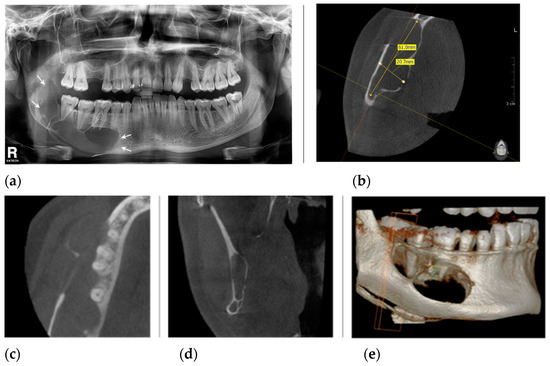

2. Case Presentation